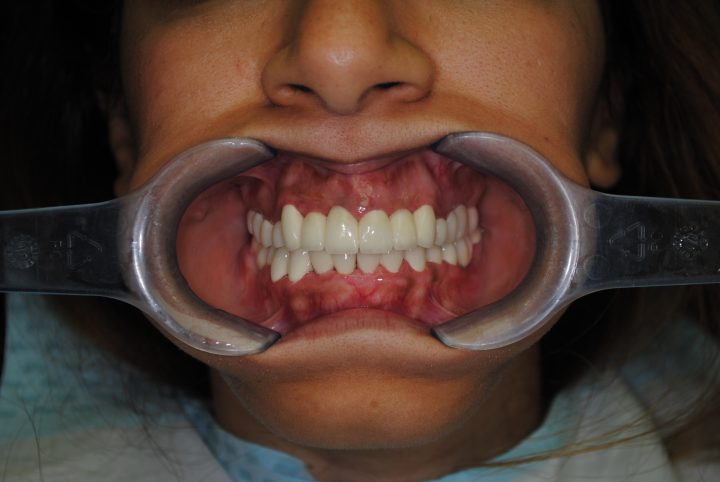

So, nach der 14 Wochen langen Heilungszeit, im Oktober 2017ist er zweites Mal nach Budapest geflogen, wann er oben und unten insgesamt 28 Stück metallfreie Zirkon Kronen im Ablauf 12 Tagen bekommen hat.

Peter macht noch immer Drachenflieger, aber trägt immer Zahnschienen zum Fliegen.